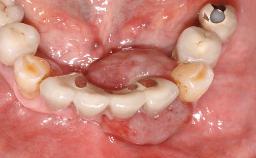

Oral implants are highly successful and offer long-term benefits, especially in the rehabilitation of edentulous patients or patients with oral defects following ablative tumor surgery (Albrektsson and coworkers 1986), and also after radiation therapy (Schiegnitz and coworkers 2014). With the number of implants placed globally going into the millions, implant dentists have observed some rare adverse events. Although carcinogenesis around implants is an exceedingly rare phenomenon, we recently reported about 15 patients treated for carcinomas adjacent to implants at our clinical department over a period of fifteen years (Moergel and coworkers 2014). The following case represents a patient of this cohort; it discusses possible risk factors and makes suggestions for a recall schedule. A 70-year-old woman was referred to our outpatient department for evaluation of a rapidly growing macroscopic alteration of the mucosa in the left mandible.

| # of Teeth | 7 |

| # of Implants | 4 |